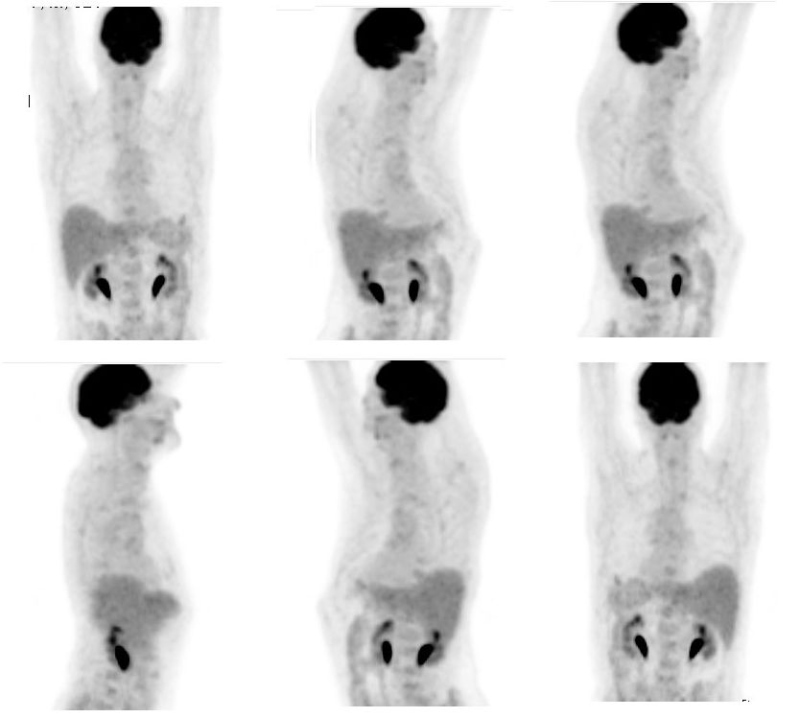

Tanto en el estudio PET corporal (fig. 5) como el PET-CT torácico (fig.6) se detecta la ausencia de hallazgos significativos en lóbulo pulmonar superior izquierdo y en regiones ganglionares hilio-mediastínicas, lo cual refleja una muy buena respuesta al tratamiento concomitante de QT y RT y por tanto remisión completa de la enfermedad.